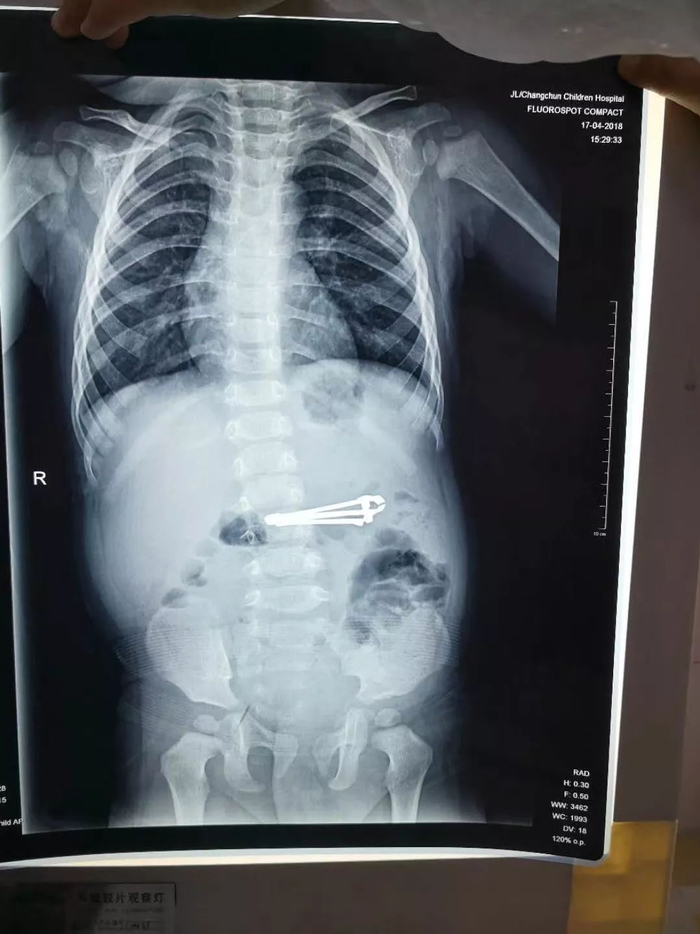

看到眼前的情形,飞飞妈妈吓坏了,抱着孩子就跑到了儿童医院,门诊医师听到家长介绍情况后,马上开启了绿色通道。门诊外科第一时间给飞飞拍了胸片,与此同时,通知麻醉科进行手术准备。“胃的排空时间大概是4-6小时,孩子从吞指甲刀到来医院就医,大概30分钟左右,可以断定,指甲刀一定在胃里。”内镜科副主任医师边鹏说,胸片显示指甲刀有6公分,大家都清楚指甲刀的锋利,当时的情况,就是尽可能的抢时间,取出异物,防止指甲刀进入肠道,造成大出血穿孔,进而给孩子带来生命危险。

(胸片显示指甲刀有6公分)